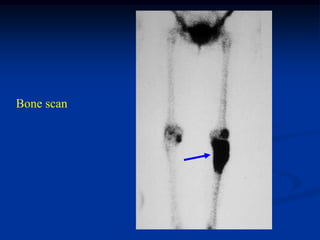

Bone scan

Sagittal T-2 MRI